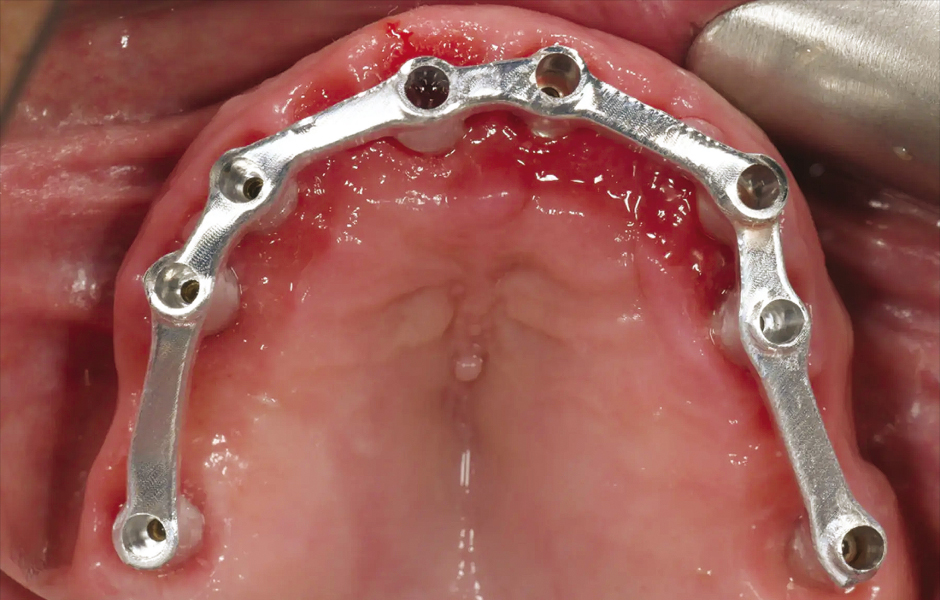

Obr. 6: Chirurgická šablona bez kovových pouzder pro přípravu fixačních pinů.

Obr. 7: Chirurgická šablona bez kovových pouzder pro plně navigovanou implantaci.